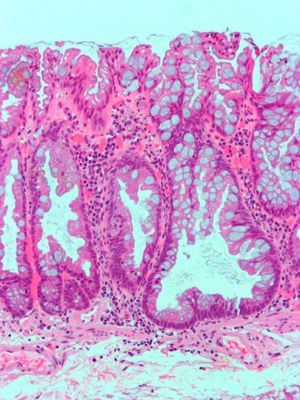

| 관상 선종 (융모상, 관상융모상) | 대장 | 신장된 핵을 가진 관상 샘 (최소한 낮은 등급의 비정형) | 예 | ![]() | |

| 관상 선종 (융모상, 관상융모상) | 대장 | 신장된 핵을 가진 관상 샘 (최소한 낮은 등급의 비정형) | 예 | ||